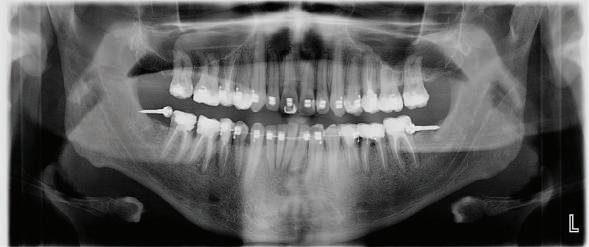

Пациент: 30 г., мъж Първо посещение: 02.08.2018 г. Основни оплаквания: Лицева болка, главо болие и болка в дясната темпоромандибу ларна става, естетични съображения РАБОТЕН ПРОТОКОЛ:

диагностика терапия със сплинт ортодонтска рехабилитация диагностична реоценка вертикален размер на оклузията –диагностичен восъчен моделаж протетична рехабилитация работа в зъботехническата лабора тория диагностична реоценка поддръжка

СПИСЪК С ПРОБЛЕМИ:

тясна зъбна дъга – горна и долна струпване във фронта – в горна и долна челюст вертикален излишък в максилата, водещ до скелетна гингивална усмивка недобри амалгамени и композитни обтурации наличие на мъдреци 18, 38, 48 – стръм на

установяване на клас I функционално водене с канинова защита елиминиране на дисталните блокажи

ЛЕЧЕБЕН ПЛАН: екстракция на мъдреците възстановяване на компрометирани те зъби и ендодонтски релечения терапия със сплинт гингивектомия в горна челюст ортодонтско лечение: – нивелиране и подреждане на зъбите в горна и долна челюст;

– интрузия на цялата горна зъбна дъга; – дъга Gummetal с tip-back извивки в до лна челюст за нивелиране на крива та на Шпее; – ретенция. VTO – диагностичен восъчен моделаж след финалната кондилография: проме ни в оклузалната равнина; промени в относителния кондиларен наклон протетична рехабилитация

Пациентът постъпи в моята клини ка с наличие на темпоромандибуларен дисфункционален болков синдром, едно странно изместен диск с редукция в дяс ната става, клас II, подклас 2, тесни гор на и долна челюст със струпване, дъл бок овърбайт

орални снимки и снимки на позата, пал пация на мускулите, брукс-чекър, оклу зограми, кондилография, рентгеногра фии, СВСТ и ядрено-магнитен резонанс на темпоромандибуларните стави). Преди началото на ортодонтското лечение всички стари възстановява ния бяха свалени и бяха заменени с дъл госрочни временни от хибридна керами ка. На девитализираните зъби бе прове дено ендодонтско релечение. Индивиду ализиран оклузален сплинт бе направен с цел да се постигне контролирано репо зициониране на долната челюст, като носенето му продължи три месеца до възстановяване на правилната позиция на ставния диск и затихване на орофаци алната болка и дискомфорт в ставата. Брекетите в горната челюст бяха за лепени, за да започне подреждането и нивелирането на зъбите, докато паци ентът все още носеше сплинта. След края на терапията със сплинта бе на правена кондилография, за да се потвър ди триизмерната позиция на долната челюст. След залепване на брекетите в долна

тация на долната челюст. Дъга GUMMETAL с tip-back извивки бе поставена в долната челюст за ниве лиране кривата на Шпее. Случаят бе финализиран с 19x25 SS дъги в горната и долната зъбна дъга за координиране. Преди да се изготви финалният восъ чен моделаж, естетичните и лицеви те характеристики бяха анализирани с помощта на дигитален дизайн на ус мивката, за да се създаде мок-ъп, чии то форма и размери да бъдат одобрени от пациента. Бе оценена фонетиката и бяха заснети лицеви снимки и видеа. Зъ бите бяха изпилени, като препарация та бе изцяло водена от функционалния восъчен моделаж, прехвърлен в устата на пациента. След препарацията восъч ният моделаж бе напаснат и насложен върху препарационния модел и бе фрезо ван от e-max multi bl 1. Циментирането на финалните конструкции бе направе но при изолация с кофердам, следвайки адхезивния протокол. След циментирането бе направено проследяване на оклузията чрез снема не на отпечатъци, монтиране на моде лите в артикулатор в окончателната интеркуспидация и внимателно прове ряване за наличие на блокажи при воде ни движения.

В конкретния случай комбинирах златния стандарт при статична по зиция с динамична оценка на функци ята на темпоромандибуларната ста ва, за да диагностицирам и лекувам ней ната дисфункция.

Д-р Манол Ивчев, България, зт. Leandro Gambogi, Бразилия

6 Dental Tribune Bulgarian Edition / октомври 2022 г. КРАТКО ОПИСАНИЕ НА КЛИНИЧНИЯ СЛУЧАЙ

оклузална равнина ендодонтски проблеми – 15, 25, 35, 36, 37, 45, 46, 47 отклонение на срединната линия с 2 мм вляво в долна челюст мускулни болки ДИАГНОСТИКА: скелетен клас II зъбен клас II функция: ограничения в движенията –мускулни проблеми; хлабави лигамен ти – латеротрузивни странични про блеми при медиотрузия вдясно; девиа ция на долната челюст вляво. ЦЕЛИ НА ЛЕЧЕНИЕТО: разширяване на горната и долната зъбна дъга промяна на оклузалната равнина в по сока надолу – намаляване на наклона на оклузалната равнина, така че да стане по-плоска, и постигане на пра вилна оклузална равнина дистално намаляване на вертикалния размер на оклузията (LFH)

и гингивална усмивка. Започнахме лечението с пълна диагно стика (анамнеза, интраорални, екстра

та челюст 4 минивинта (TADs) бяха по ставени в максилата – 2 в небцето и 2 интрарадикуларно във фронта, с цел да се извърши интрузия на цялата зъбна дъга, да се коригира гингивалната усмивка и да се позволи провеждането на обратна на часовниковата стрелка авторо

След стабилизира не на ставите и долната челюст в те рапевтична позиция постигнах орто донтски премествания и скелетни ко рекции, които обикновено са възмож ни единствено посредством ортогнат на хирургия. Преминах от аналогов мо дел на работа към изцяло дигитален, за да се хармонизира лицевата естетика чрез Digital Smile Design, като същевре менно обаче изработих функционален аналогов восъчен моделаж и на двете че люсти, за да мога да приложа оклузална та концепция на Славичек. След което напаснах препарациите с аналоговия во съчен моделаж при изцяло дигитални ус ловия с цел фрезоване на короните. Всич ки тези комбинации правят случая из ключително комплексен. В крайна сметка този сложен случай бе лекуван с най-добрата възможна ком бинация от възможности, които ана логовият и дигиталният свят предла гат, за да се постигне красота, която е следствие от отлична функция. ОКЛУЗАЛЕН „БАЛЕТ“ С РОЗОВАТА ЕСТЕТИКА Клиничен случай, победител в категория „Комплексно естетично възстановяване“ в конкурса „Усмивка на годината 2022“ Преди След

7Dental Tribune Bulgarian Edition / октомври 2022 г. Преди лечението Фиг. 1 Фиг. 4 Фиг. 7 Фиг. 10 Фиг. 13 Фиг. 16 Фиг. 17 Фиг. 18 Фиг. 19 Фиг. 20 Фиг. 11 Фиг. 14 Фиг. 12 Фиг. 15 Фиг. 8 Фиг. 9 Фиг. 5 Фиг. 6 Фиг. 2 Фиг. 3